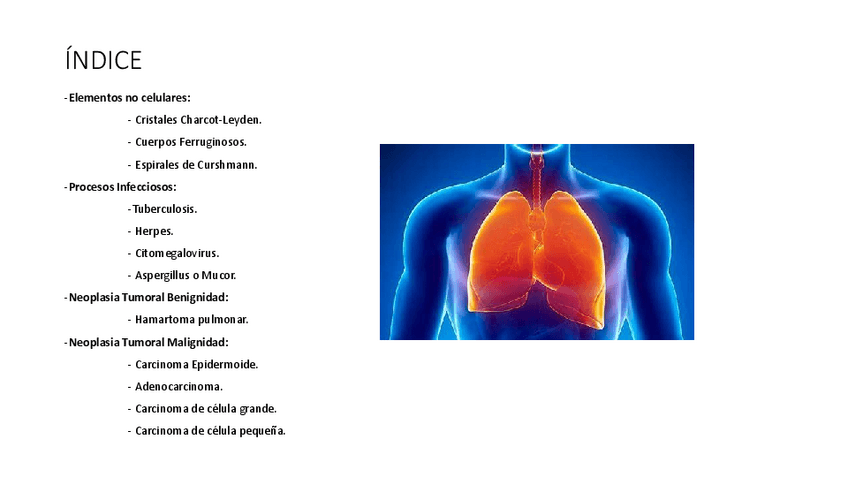

He publicado nuevos trabajos de Citología general: Liquido-Pleural.pdf

19 páginas